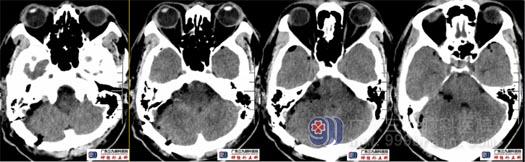

术前头颅CT示右侧桥小脑角区囊实性占位,以囊性为主,实性部分主要在内听道口,病变内血供不丰富,邻近部分血管稍受压,病灶局部突入右侧内听道;右侧内听道较对侧轻度扩张,未见骨质破坏。